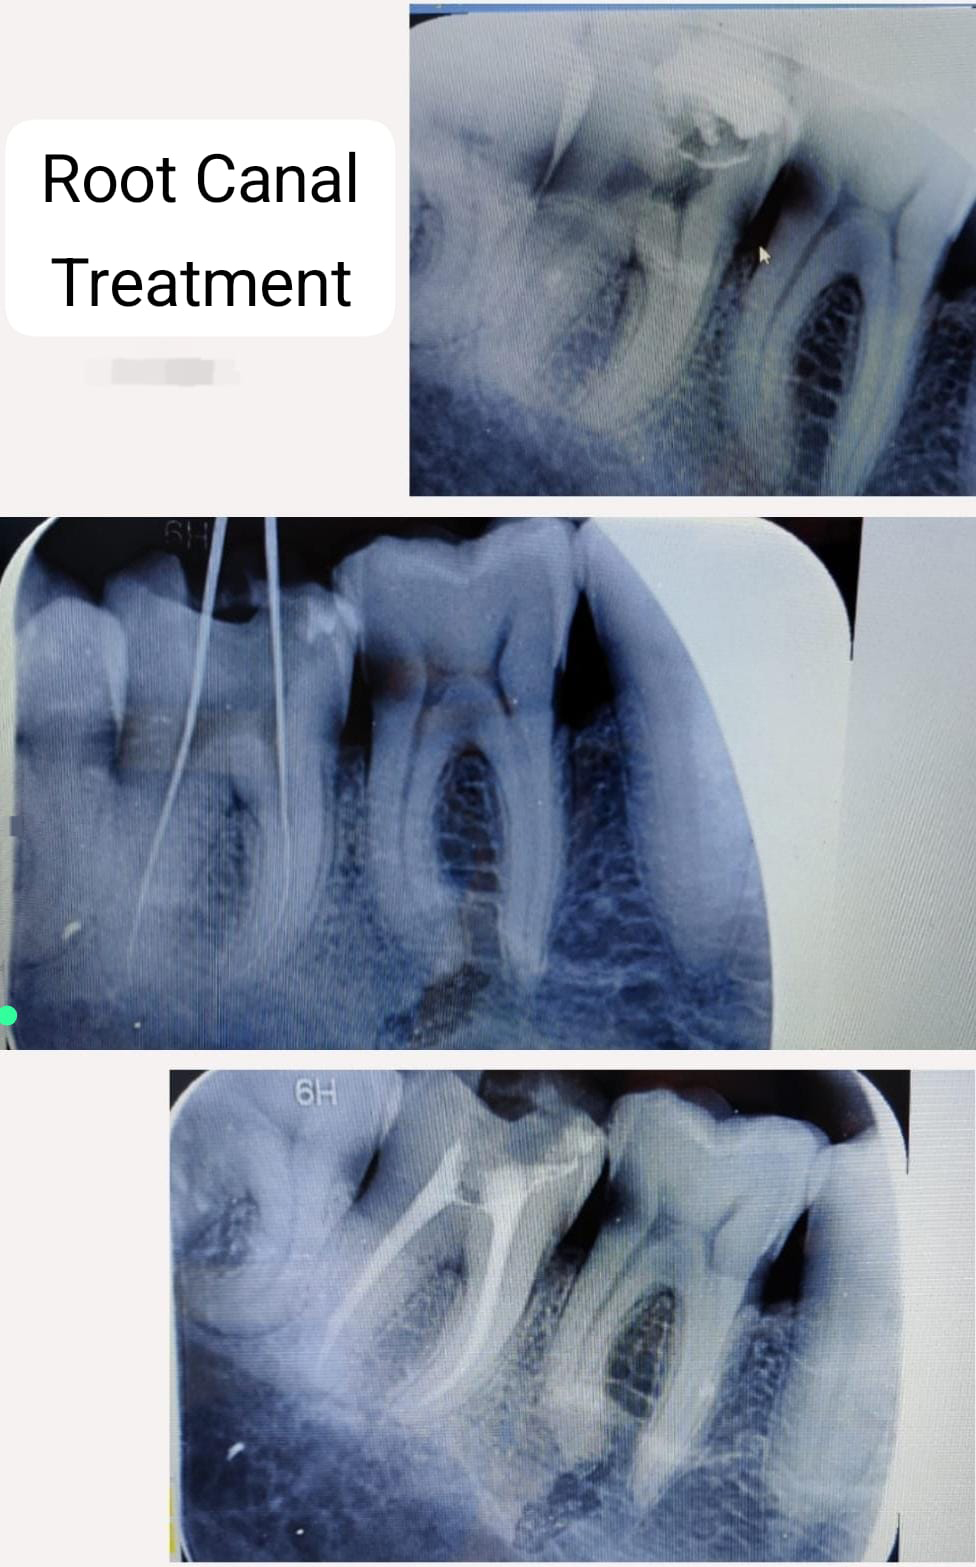

Root Canal Treatment

Single Sitting RCT